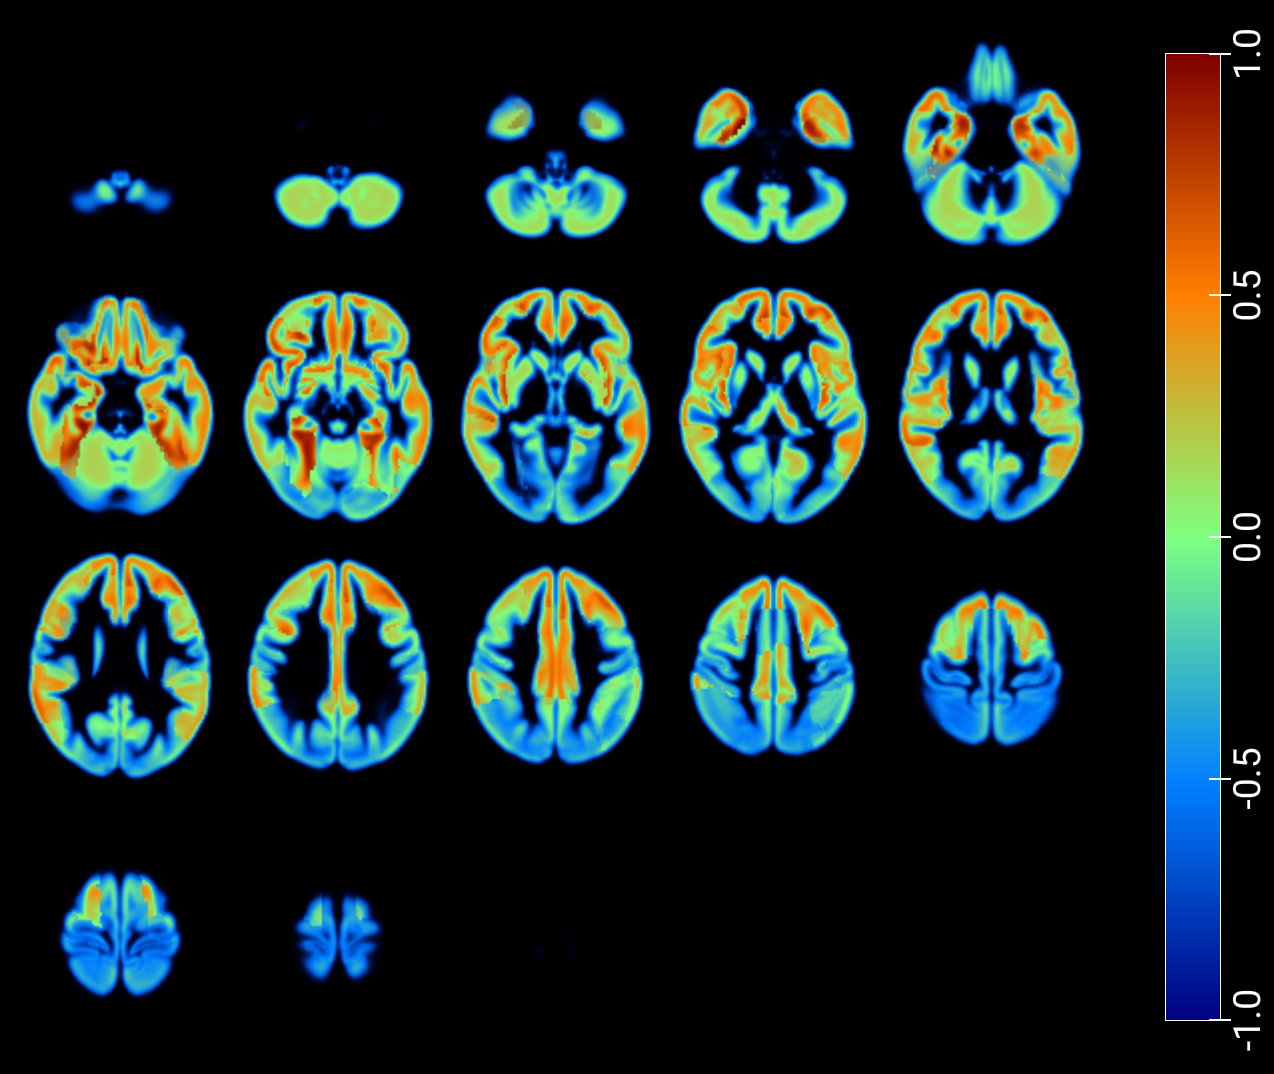

As a critical baseline, we report classification results based on latent features in [2] and provide visualizations of the maximum Pearson correlation values between latent-space activations -projected onto low-dimensional spaces- and region-wise average intensities, stratified by class, and fused with GM MRI (figures 7 and 8). These results explore the correspondence between network activations and anatomical signal distributions and whether it differs across clinical conditions (e.g., AD vs. NOR). This offers a transparent alternative to assess model interpretability and underscores the need for more rigorous and nuanced validation practices in the field.

An inspection of the groups and regions with the highest correlations reveals overlapping areas across clinically relevant comparisons in image reconstruction, as summarized for the t-SNE–based projections in Table 2. These regions correspond closely to those identified through the SHAP analysis presented in the following section (Table 3).

Finally, we applied the Latent–Regional Correlation Profiling (LRCP) framework to generate spatial maps that highlight how latent components relate to regional brain variation across different diagnostic comparisons. Specifically, we focused on the three binary groups and, for each case, projected the regional accuracy of the latent–region associations onto an anatomical atlas. By computing corrected significance rates for each latent–region pair and averaging them across subjects, we obtained accuracy maps that indicate which brain regions consistently encode discriminative information for each comparison. These maps provide an interpretable visualization of the spatial distribution of diagnostic relevance, facilitating a region-wise comparison of how latent dimensions capture biologically meaningful variation across the different binary groups.